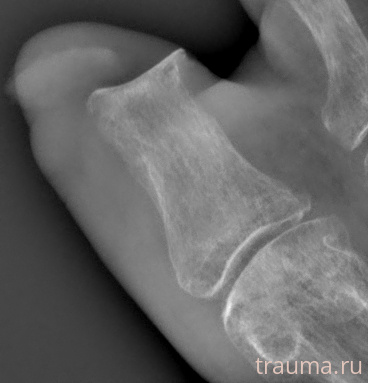

Рентген на дому: по вашему адресу приезжает врач-рентгенолог, травматолог-ортопед с мобильным рентгеновским аппаратом, проводит диагностику травмы или заболевания, делает необходимые рентгенограммы, дает рекомендации по дальнейшему лечению. Получить качественные снимки в домашних условиях возможно благодаря уникальной методике, разработанной МосРентген Центром для института  Склифосовского

при переломе шейки бедра и пневмонии от компании МосРентген Центр - партнера Института имени Склифосовского